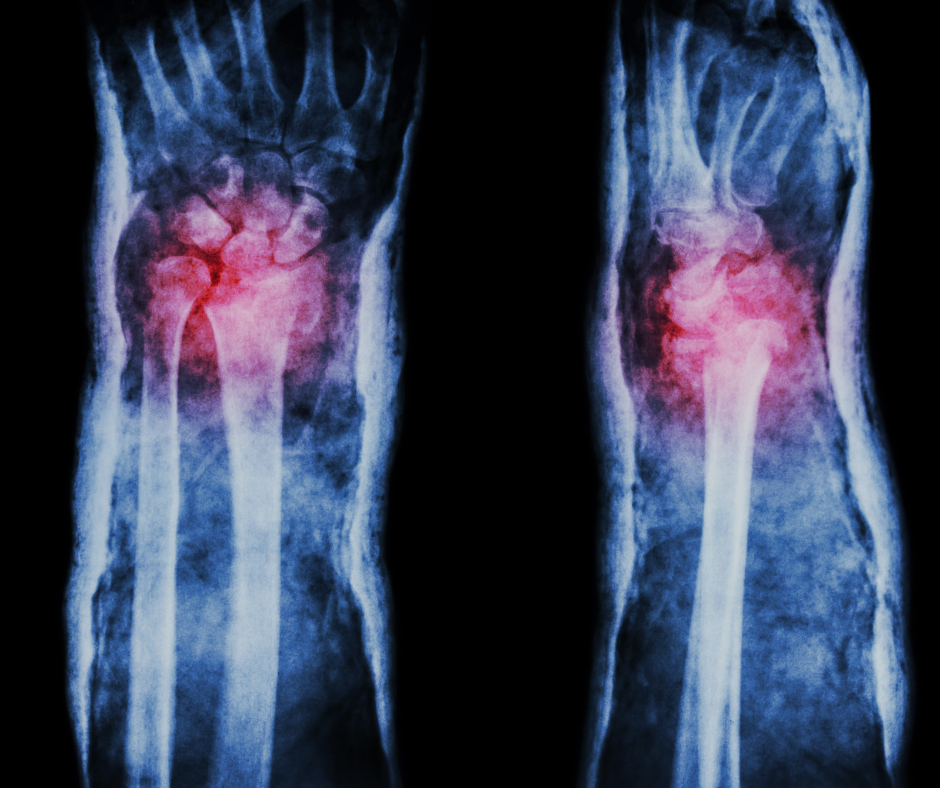

As fraturas do rádio distal são muito comuns, especialmente após quedas sobre a mão estendida. Apesar de serem conhecidas[…]